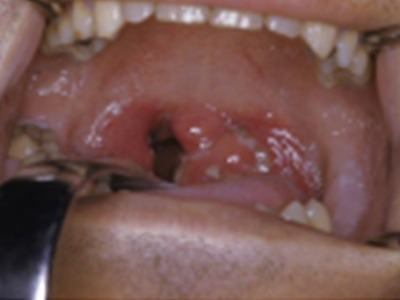

扁桃体

红肿 · 充血

急性隐窝性扁桃体炎扁桃体肿了图

急性隐窝性扁桃体炎患者扁桃体出现充血、红肿,表现为单侧肿大,并伴有不同程度的疼痛感以及吞咽困难,严重者伴有睡眠打鼾的情况。